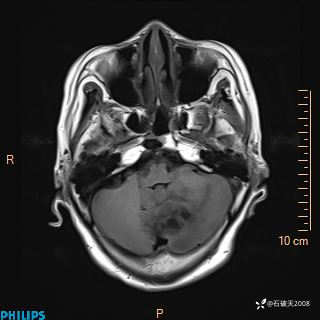

书上说这个肿瘤发生在幕下仅4.09%,你会想到它吗?(病理已公布)

女 86岁 主 诉:乏力1月

现病史:患者1月前活动出现双下肢乏力,无头晕、头痛、恶心、呕吐、肢体活动不利,休息后缓解,间断断发作,症状进行性加重,在家口服药物治疗(具体不详),效差,为进一步诊治,来我院,门诊按“乏力”收住我科,患者自发病以来,神志清,精神稍差,饮食睡眠欠佳,大小便正常,体重未见明显改变。

T1